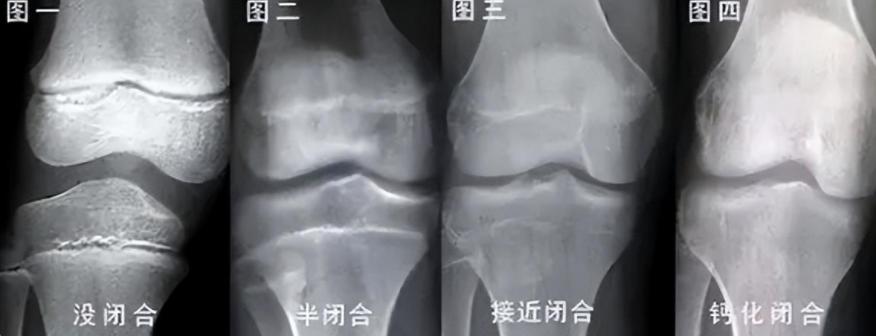

“医生”在李亚诺的小腿胫骨处截骨,截开之后再用钢钉按位置打进骨髓腔,再用石膏进行固定,并安装牵引支架,以便术后拉伸。

在术后的第五天,李亚诺开始了第一次“增长”,他躺在床上, 医生用设备对其切割处进行牵拉,疼痛贯彻神经,拉伸过程中,血管、皮肤组织都会被拉长。

而这一系列的操作下来,李亚诺也才“长高”了半毫米,他疼得鼻涕一把泪一把,可这样的牵拉他还要经历很多次。

李亚诺最终将双腿拉长了7.2厘米,身高达到了1.74米,可想而知他经历了怎样的剧痛。

接下来就是术后的恢复,这是个漫长的过程,普通手术3至5个月就能恢复完毕,但断骨手术的恢复时间要达到一年,还只是可以下地行走,不能剧烈运动。